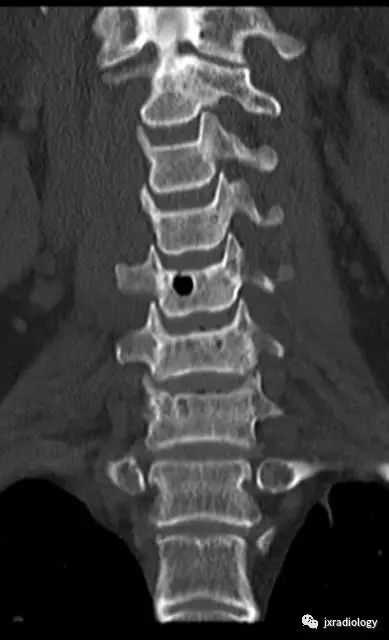

颈腰椎CT片,看到椎骨里的气体密度影,你会考虑什么?相信很多同行朋友会有此类困惑。今天带大家一起学习下该病。

影像资料:

CT:被认为是最好的诊断方法,CT值约-800~-1000HU,椎体及椎间隙内可见气体可以看到相连续的层面,有时会向硬膜外扩张。MRI:气体在T1及T2均为低信号,易和硬化性病变混淆,CT有助于诊断。随访发现一些病灶会增大,但不需要特别治疗。